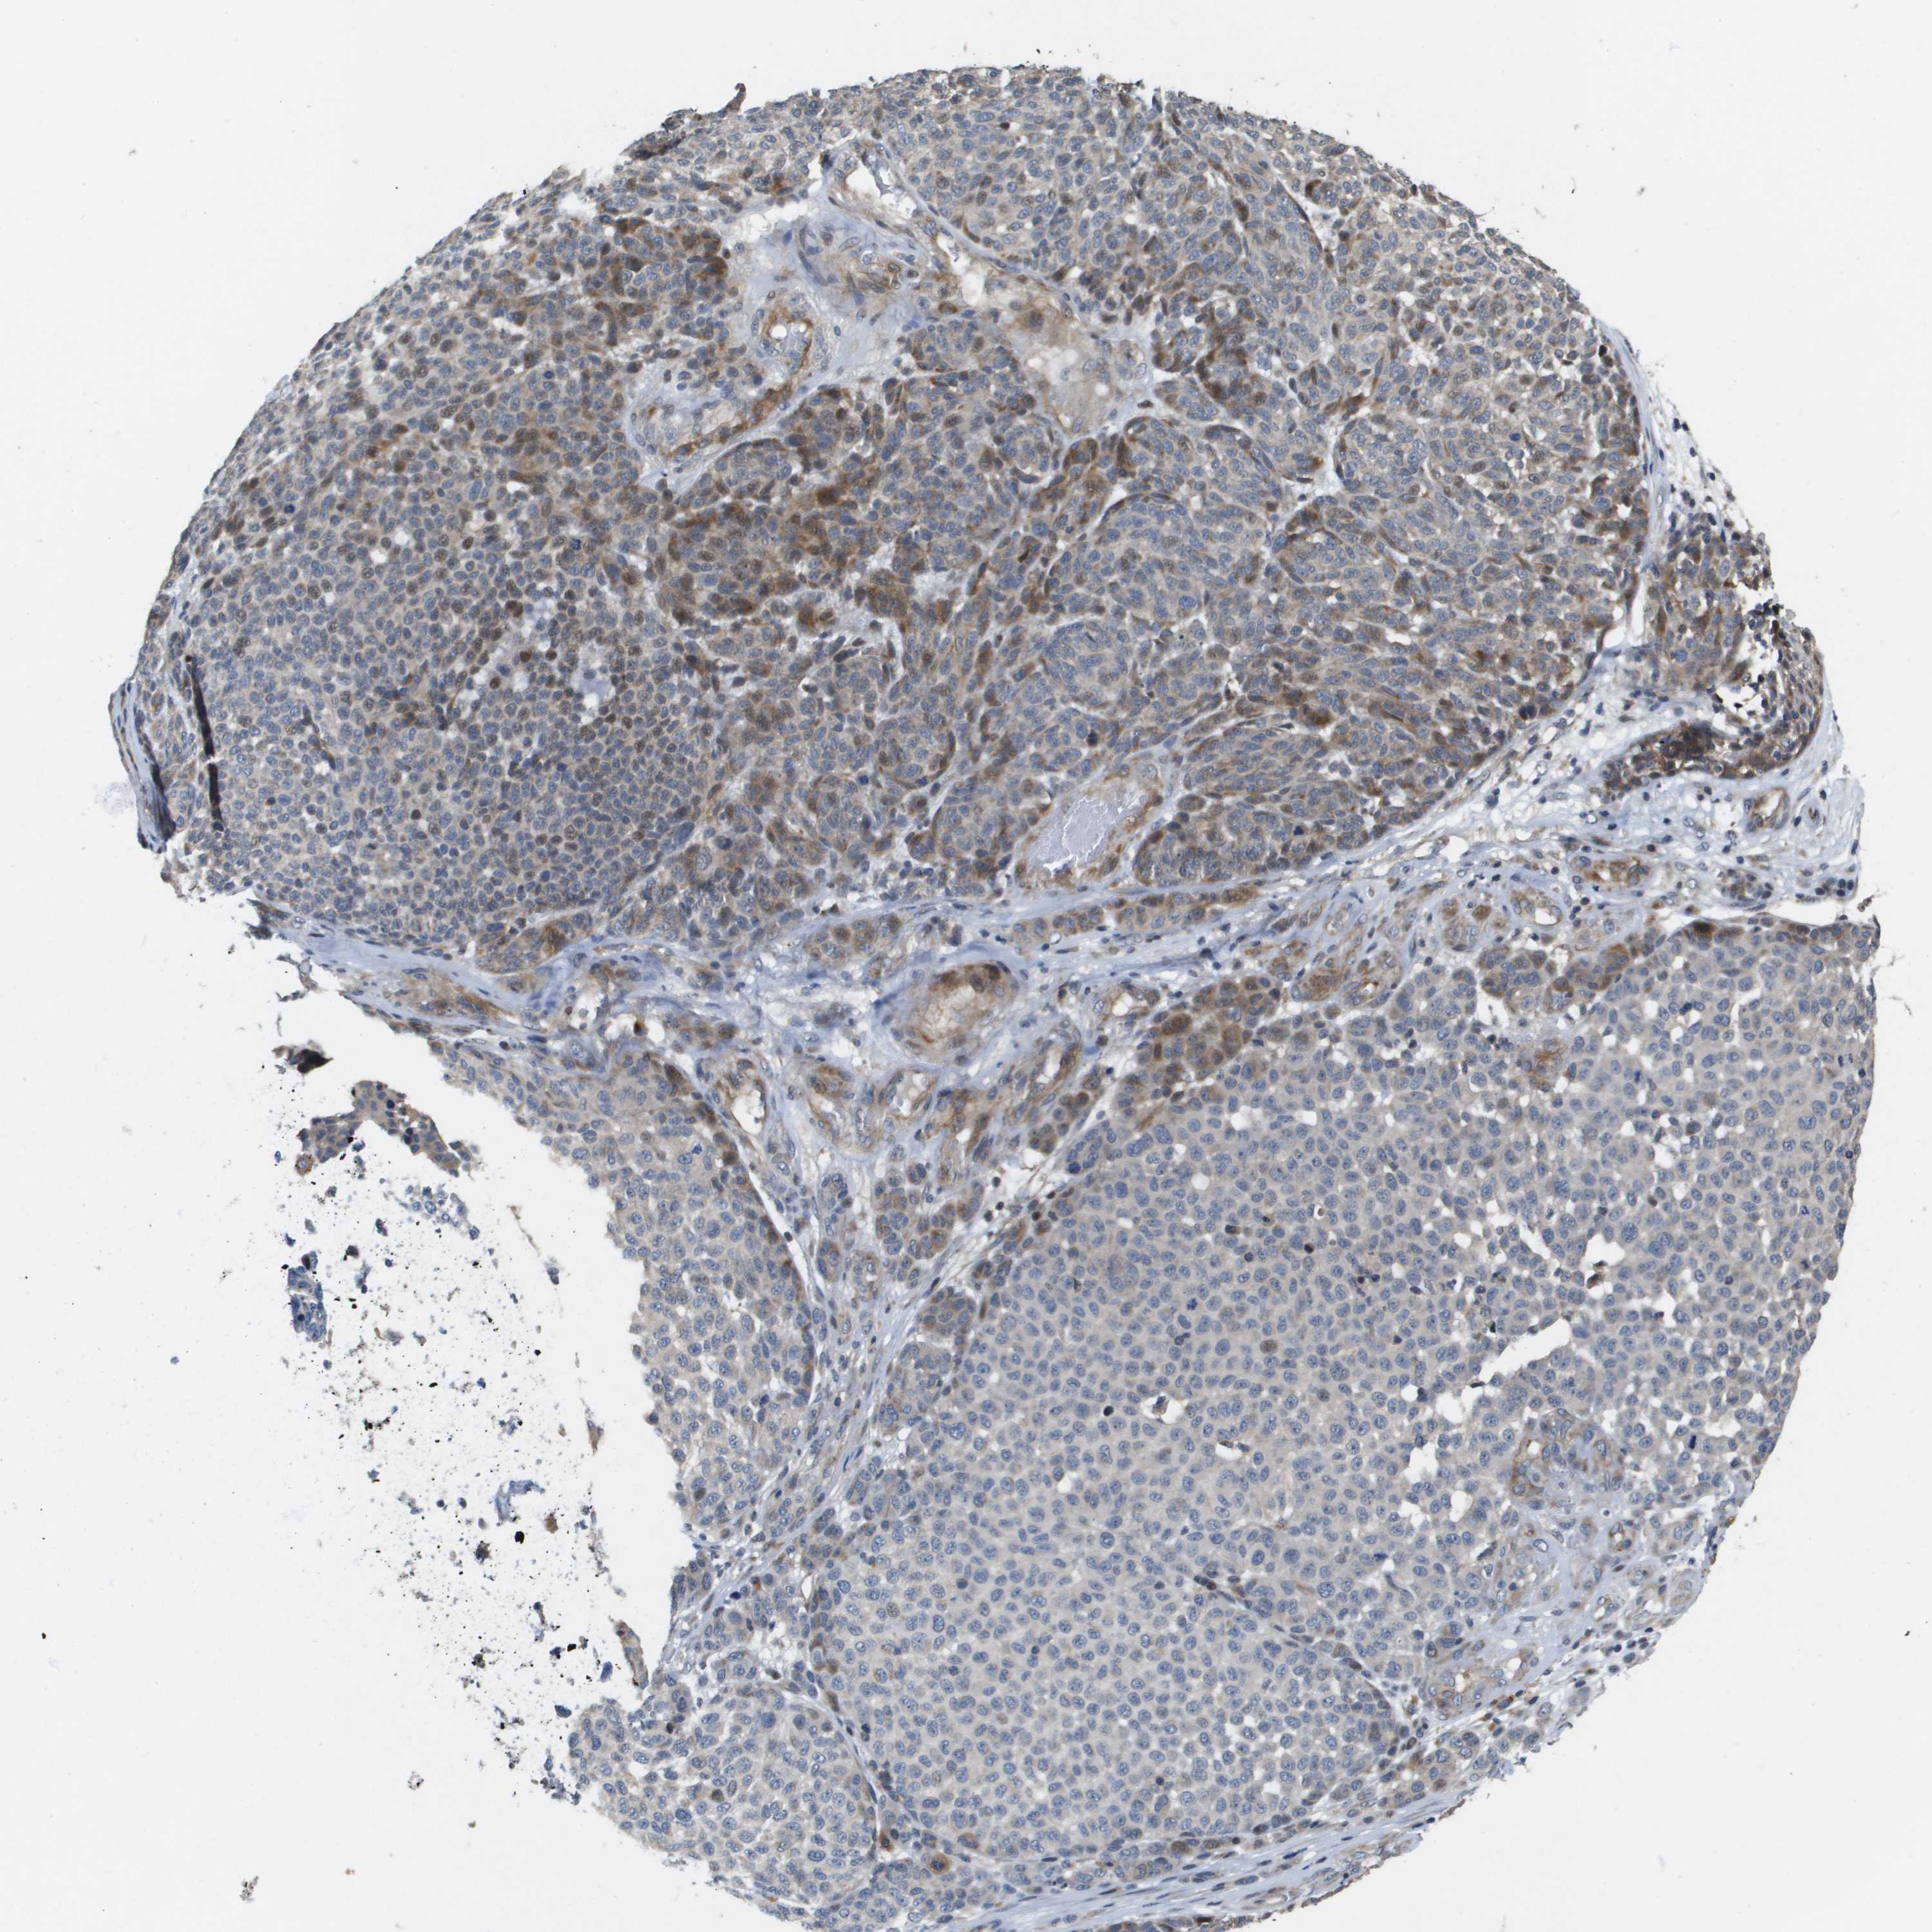

MELANOMA - Protein expressioni

A mouse-over function shows sample information and annotation data. Click on an image to view it in a full screen mode. Samples can be filtered based on level of antibody staining by selecting one or several of the following categories: high, medium, low and not detected. The assay and annotation is described here.

Note that samples used for immunohistochemistry by the Human Protein Atlas do not correspond to samples in the TCGA dataset.

Antibody stainingi

Antibody staining in the annotated cell types in the current human tissue is reported as not detected, low, medium, or high, based on conventional immunohistochemistry profiling in selected tissues. This score is based on the combination of the staining intensity and fraction of stained cells.

Each image is clickable and will lead to virtual microscopy that enables deeper exploration of all samples and also displays staining intensity scores, fraction scores and subcellular localization as well as patient and tissue information for each sample.

Antibody HPA017293

Staining

High

Medium

Low

Not detected

Intensity

Strong

Moderate

Weak

Negative

Quantity

>75%

75%-25%

<25%

None

Location

Nuclear

Cytoplasmic/membranous

Cytoplasmic/membranous,nuclear

Malignant melanoma, NOS

Malignant melanoma, Metastatic site